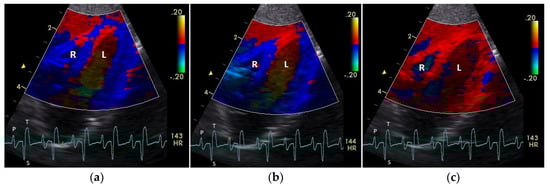

Figure 2.

Color coding of the early (a), middle (b), and late part (c) of systolic tissue velocities by tissue Doppler imaging from the four-chamber view: the movement of the myocardium toward (red color) and away from the heart apex (blue color) is visible. R: right; L: left ventricle; HR: heart rate. Electrocardiogram: P: P wave; S: S wave; T: T wave. The color scale on the right of the image is calibrated in cm s−1.

The positive S’ wave of the TDI curve (Figure 3 and Figure 4; ascending part of the S wave to the descending part of the T wave of the ECG) describes the systolic movement of the heart base toward the heart apex and represents the expulsion phase of the heart. In the middle of the S’ wave of the TDI, there is little movement of the heart apex toward the heart base and the myocardial velocities are negative (Figure 2). This movement in the middle part of the systole led to an irregular shape of the S’ wave in the TDI curve (Figure 3). The negative E’ wave (Figure 3 and Figure 4; after the T wave of the ECG) in the TDI curve describes the movement of the myocardium during the passive ventricular filling and the second negative A’ wave of the TDI curve (Figure 3 and Figure 4; P wave of the ECG) describes the movement of the myocardium in the active filling phases of the heart during the diastole away from the heart apex. Before and after the S’ wave, the TDI curve showed undirected deflections as a sign of isovolumetric contraction (IVC) and relaxation (IVR; Figure 3 and Figure 4). However, the transition between the A’ and S’ waves (IVC) and the S’ and E’ waves (IVR) could be flowing and sometimes difficult to see.